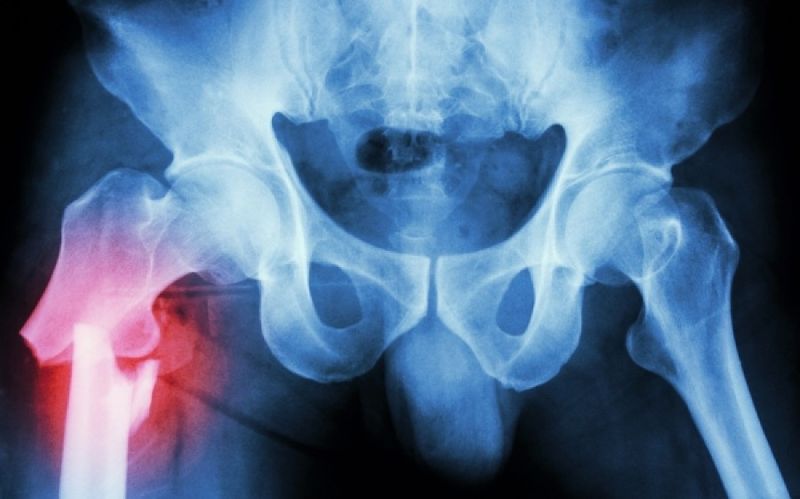

Η τροχαντηρίτιδα είναι φλεγμονή στην άρθρωση του ισχίου ανάμεσα στους γλουτιαίους μύες και τον μείζονα τροχαντήρα, την οστική προεξοχή που βρίσκεται στο πάνω μέρος του μηριαίου οστού.